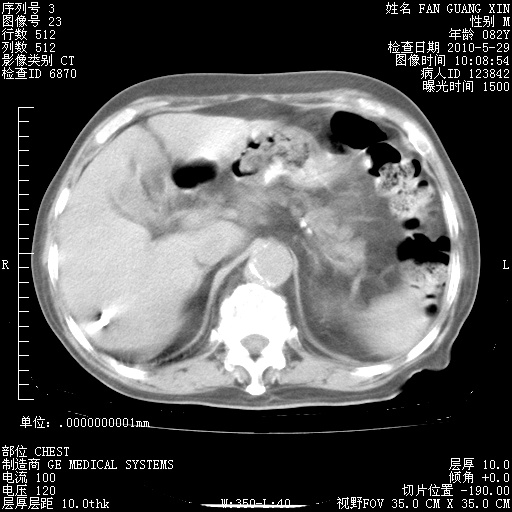

再治疗10天后的肺部CT 纵膈窗

阅读此次胸部CT,肺间质渗出性改变较入院时有吸收。目前从体温、白细胞、中性分叶明显增高,肯定存在细菌感染(发生医院感染哦,若无消化道及泌尿系统等感染的依据,肺部感染可能大)。若你院头孢哌酮舒巴坦钠耐药率较高,同意你的方案,若48小时体温仍高,可考虑使用碳青霉稀类抗菌药物,同时可予超声雾化、注意滴数时加大液体量。白蛋白33.30g/L较低哦,需加强营养等支持治疗。